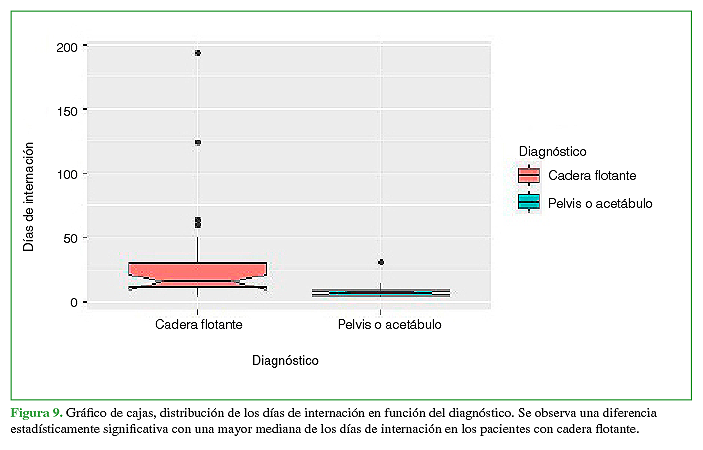

Resumen: Objetivo: Describir los tiempos de internación, cirugía y rehabilitación de una serie de pacientes con cadera flotante. El objetivo secundario fue comparar los resultados obtenidos en función de la reinserción laboral con los de pacientes que sufrieron fracturas de pelvis o acetábulo sin fractura femoral asociada. Materiales y Métodos: Estudio descriptivo, retrospectivo y multicéntrico de pacientes con trauma de pelvis y acetábulo de alta energía, divididos en dos grupos de estudio según la presencia de fractura de fémur asociada homolateral (cadera flotante) para su comparación, durante el período comprendido entre enero de 2014 y marzo de 2019. Resultados: Se incluyó a 102 pacientes con trauma de pelvis o acetábulo agrupados en 2 poblaciones según la presencia de cadera flotante (cadera flotante 23; pelvis/acetábulo 79). Las medianas de días de internación [cadera flotante 15,5 (rango 4-193); pelvis/acetábulo 7 (rango 3-31); p = 0,0001] y de la cantidad de cirugías por paciente [cadera flotante 5 (rango 3-8); pelvis/acetábulo 2 (rango 1-4); p = 0,0001] fueron mayores en los pacientes con cadera flotante. Además, la incapacidad laboral temporaria fue más alta (p = 0,00012), sin diferencias significativas en la tasa de recalificación laboral (p = 0,11). Conclusión: La asociación de la lesión cadera flotante aumentó significativamente el tiempo de internación, los procedimientos quirúrgicos necesarios y el tiempo de recuperación según la incapacidad laboral temporaria en pacientes con trauma de pelvis o acetábulo.

Abstract: Objective: We aim to describe the lengths of hospitalization, surgery, and rehabilitation of a series of patients with floating hip. As a secondary objective, to compare the outcomes obtained in terms of return to work in patients who had suffered fractures of the pelvis or acetabulum without an associated femoral fracture. Materials and Methods: Descriptive, retrospective, and multicenter study of patients with high-energy trauma to the pelvis and acetabulum divided into two study populations according to the presence of associated ipsilateral femur fracture (floating hip) for comparison, during the period January 2014 - March 2019. Results: 102 patients with pelvis and/or acetabulum trauma were included, grouped into 2 populations according to the presence of a floating hip (Floating hip: 23 patients; Pelvis/acetabulum: 79 patients). The median days of hospitalization [floating hip: median = 15.5 (range = 4-193); pelvis/acetabulum: 7 (3-31); p = 0.0001] and the number of surgeries per patient [FH: median = 5 (range = 3-8); pelvis/acetabulum: 2 (1-4); p = 0.0001] were higher in patients with floating hip. Additionally, temporary work disability was higher (p = 0.00012), with no significant differences in the rate of job retraining (p = 0.11). Conclusion: Floating hip significantly increased the length of hospitalization, necessary surgical procedures, and recovery times according to temporary work disability in patients with trauma to the pelvis and/or acetabulum.

Al analizar estas variables en la comparación entre pacientes con CF frente a aquellos con fractura de pelvis/acetábulo, las medianas de días de internación [CF 15,5 (rango 4-193); pelvis/acetábulo 7 (rango 3-31); p = 0,0001] y de la cantidad de cirugías por paciente [CF 5 (rango 3-8); pelvis/acetábulo 2 (rango 1-4); p = 0,0001] fueron mayores en los pacientes con CF, con diferencia estadísticamente significativa en la distribución de ambas variables (Figura 9).

Se hallaron diferencias estadísticamente significativas con respecto a los tiempos de internación de ambos grupos, lo que nos llevaría a pensar en una eventual relación posible con la lesión femoral al analizar esta variable. También, habría que considerar las lesiones asociadas no ortopédicas que prolongan la internación y no fueron analizadas en el estudio. Debemos remarcar que no se encontraron artículos publicados que analicen este ítem.